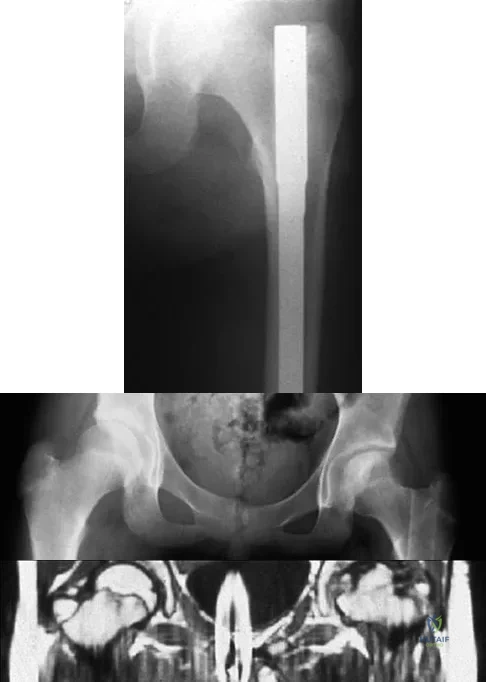

A 30-year-old man falls off a 7-foot ladder and sustains the injury seen in the radiograph and the CT scan shown in Figures 39a and 39b. Medical history is negative. Management of this injury should include which of the following?

Explanation